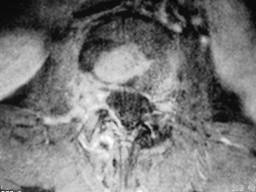

问题 男,53岁,高热,寒战,背痛半月余,请结合影像学检查选出最可能的诊断 ( )

选项 A、强直性脊柱炎 B、椎体压缩骨折 C、脊柱骨髓炎 D、脊柱结核 E、脊柱转移瘤

答案 C